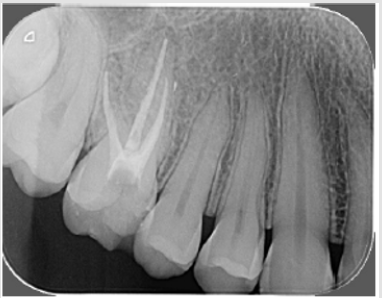

Patient M.A.R., female, 27 years old, went to Endodontic Specialization to treat the first right maxillary molar. The emergency treatment was done in a health Center one month ago. Radiography was performed (Figure 3) and the clinical examination verified the permanence of the fistula (Figure 4). After endodontic access and irrigation with 2.5% sodium hypochlorite (Iodontosul, Porto Alegre, Brazil), the MB2 was localized with # 10 C pilot file (VDW, Munich, Germany) (Figures 5 & 6). Root canal system exploration and electronic working length were performed (Romiapex A-15, Romidan Ltd, Kiryat Ono, Israel). After Glide Path with Proglider was done (Dentisply-Maillefer, Switzerland) and preparation of all channels with Wave One Gold Primary (Dentisply-Maillefer, Switzerland) (Figure 7) The smear layer was removed and calcium hydroxide intracanal medication was done (SS WHITE, Rio de Janeiro, Brazil) and glass ionomer sealing (SS WHITE, Rio de Janeiro, Brazil) were placed. .Patient returns after 40 days, and on clinical examination, fistula regression is observed (Figure 4). In the second appointment, the MB1, MB2 and distal root were enlarged with Wave One Gold Medium ( Dentisply-Maillefer, Suiça) and palatine root has been expanded with Wave One Gold Large (Dentisply-Maillefer, Switzerland), smear layer was removed and obturation performed (Figures 8 & 9).

Figure 8: Clinical situation after forty days of calcium hydroxide medication, showing regression of the fistula.